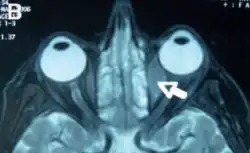

Orbital lymphoma

Orbital lymphoma is a common type of non-Hodgkin lymphoma that occurs near or on the eye. Common symptoms include decreased vision and uveitis. Orbital lymphoma can be diagnosed via a biopsy of the eye and is usually treated with radiotherapy or in combination with chemotherapy.